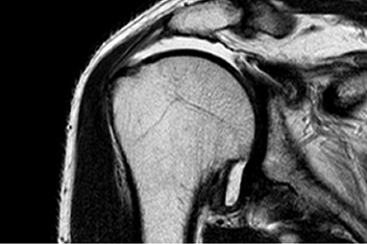

회전근개파열

회전근개 파열 MRI

회전근개손상

회전근개는 어깨 주변을 덮고 있는 4개의 힘줄을 통칭하며, 어깨를 지탱해주고

팔을 들어올리는 등 어깨의 운동을 원활하게 해주는 기능을 합니다.

이러한 현상은 비정상적인 힘이 가해지거나 퇴행성 변화로 인해 생기며,

약해지면서 회전근개가 파열되며, 가장 흔한 어깨 통증의 원인 중 하나입니다.

힘줄이 파열되면 극심한 통증과 관절 운동의 제한이 나타나며, 근력이 약해지는 특징이 있어

오십견과 감별이 필요합니다. 다만, 파열의 정도와 통증의 정도가 반드시 일치하지 않기 때문에

전문의의 진료 하에 적절하게 진단되지 않을 시에 병이 악화될 수 있습니다.